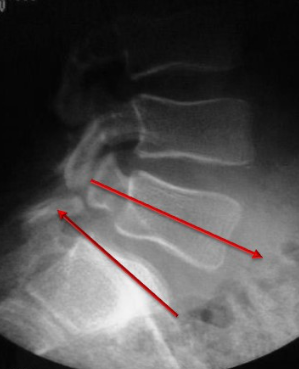

Concernant le rachis lombaire

Les processus articulaires supérieur et inférieur sont vus de profil.

Les articulations zygapophysaires du côté appuyé (D) sont démontrées.

Les pédicules du côté appuyé (D) sont projetés dans le tiers antérieur des corps vertébraux.

Les articulations zygapophysaires du côté appuyé (D) sont projetées au centre des corps vertébraux